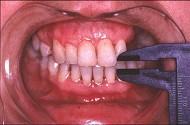

问题 患儿,5岁,外伤后逐渐出现张口困难,咬合关系错乱,髁突动度减弱,外观及X 线检查结果如图。最可能的诊断是 ( )

选项 A.颞下颌关节强直 B.颧骨骨折 C.颧弓骨折 D.下颌骨骨折 E.上颌骨骨折

答案 A